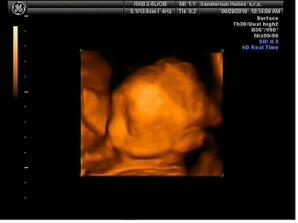

29.6. jdeme na 3D ultrazvuk 🙂 těšíme se... - bylo to úžasný 🙂 cena sice vyšší, ale jedna barevná fotka tištěná, 3 fotky na mail a téměř půlhodinové video, ze kterého jsme si doma udělali ještě asi 120 fotek 🙂